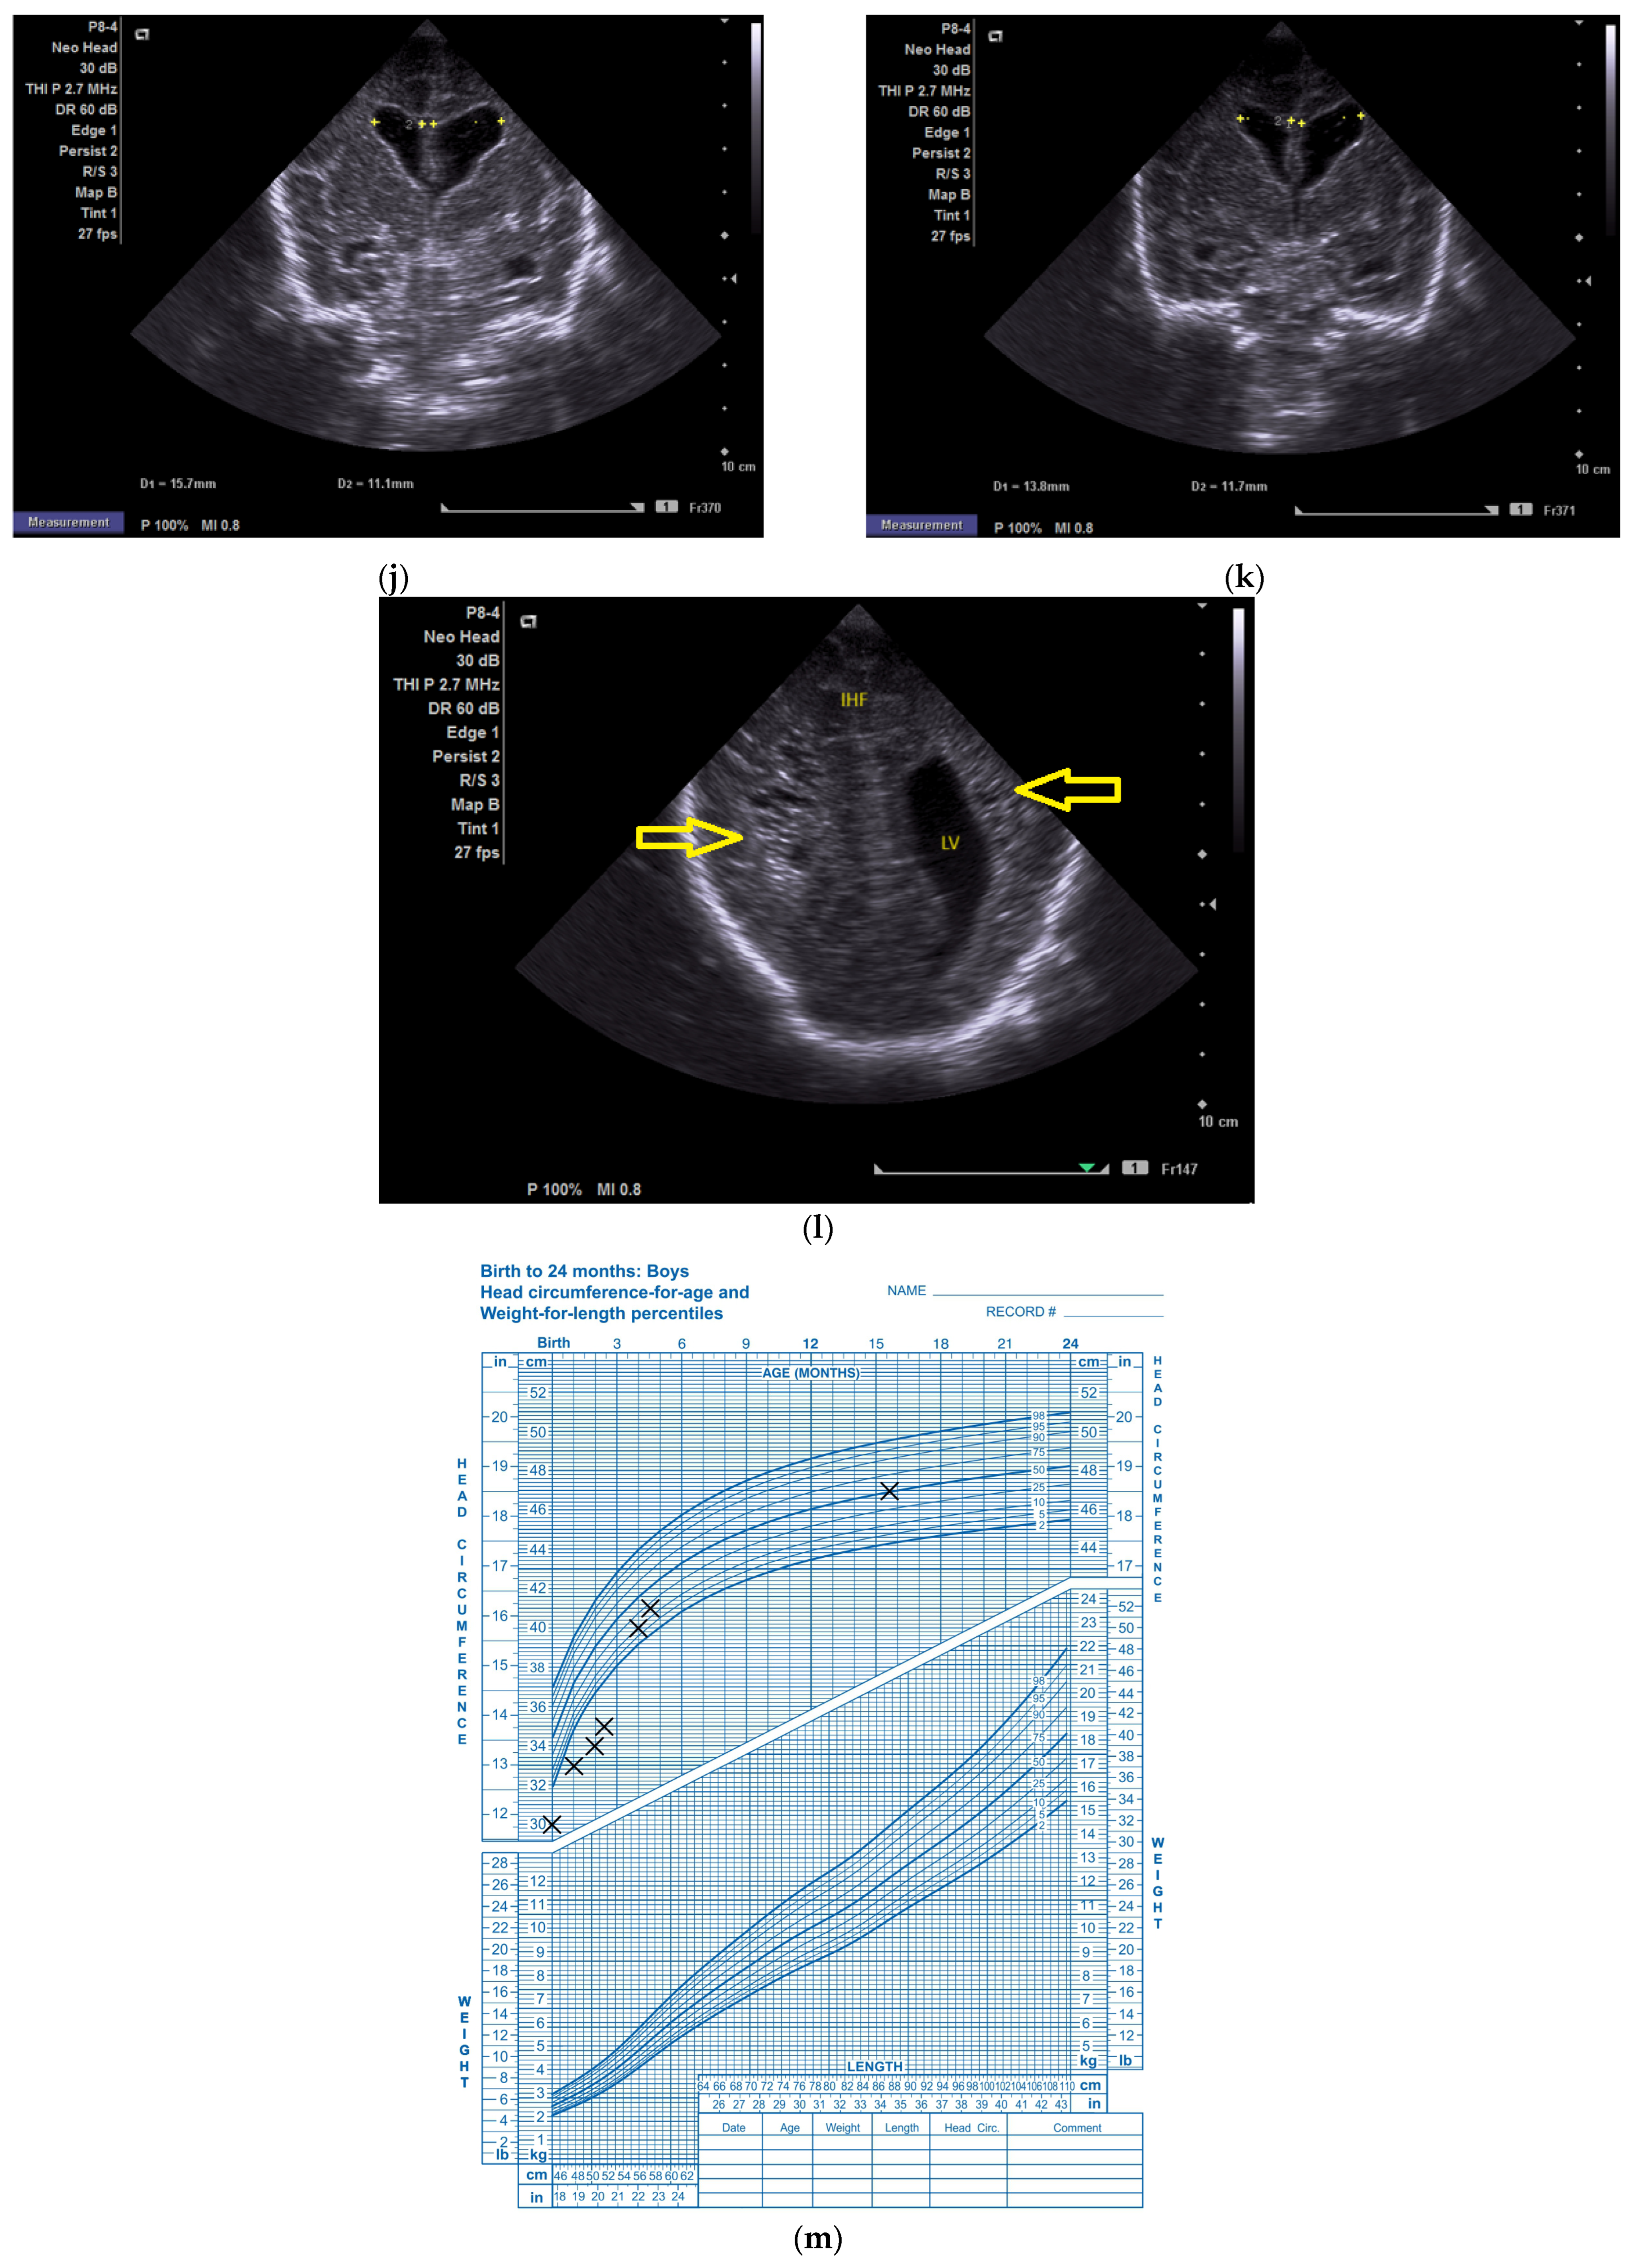

(a) Day one. Cranial ultrasound. Sagittal view. A left frontal conatal cyst can be observed. IHF—interhemispheric fissure. CG—cingulate gyrus. CC—corpus callosum. CSP—cavum septum pellucidum. TCG—thalamic-caudate groove. MF—Monroe foramina. SF—Sylvian fissure. Yellow arrow—conatal cyst (personal image collection). (b) Day three. Cranial ultrasound. Coronal view. Bilateral ventricular dilatation. Yellow arrows—hyperechoic images can be seen at the level of the thalamic-caudate groove and within the ventricles (personal image collection). (c) Day three. Cranial ultrasound. Coronal view. Orange arrows—bilateral periventricular hyperechoic images (personal image collection). (d) Day three. Cranial ultrasound—Doppler examination. Sagittal view. CC—corpus callosum. FL—frontal lobe. LV AH—lateral ventricle anterior horn. V 3—third ventricle. V 4—fourth ventricle. OL—occipital Lobe. Yellow arrow—presence of color Doppler signal within the Sylvian aqueduct (personal image collection). (e) Day 19. Cranial ultrasound. Sagittal view (left). Yellow arrows—conatal cysts. Pink arrows—PVL lesions (personal image collection). (f) Day 19. Cranial ultrasound. Sagittal view (left). Yellow arrows—conatal cysts. Pink arrows—PVL lesions (personal image collection). (g) Follow-up examination at term corrected age. Cranial ultrasound. Coronal view. Slight dilation of the lateral ventricles. IHF—interhemispheric fissure. CG—cingulate gyrus. CC—corpus callosum. CSP—cavum septum pellucidum. LV—lateral ventricle. MF—Monroe foramina (personal image collection). (h) Second follow-up examination. Cranial ultrasound. Coronal view. Dilation of interhemispheric fissure and subarachnoid space. D1—sinus–cortical width measurement. D2—interhemispheric width measurement. D3—cranio-cortical width measurement (personal image collection). (i) Third follow-up examination. Cranial ultrasound. Coronal view (left). D1—dilation of interhemispheric fissure. D2, D3—Levine index measurement (personal image collection). (j) Cranial ultrasound. Sagittal view (right). Normal brain structures (personal image collection). (k) Head circumference-for-age. “X” symbols represent the measurements performed from birth and follow-up examinations (personal image collection) [28].

On day three of life, the CUS displayed a bilateral germinal matrix hemorrhage with more than 50% of the ventricular volume being occupied by blood. Periventricular hyperechoic images could be observed as well (Figure 2b,c).

On the fourth day of life, a Doppler examination showed the presence of a signal within the third ventricle (Figure 2d).

A series of four lumbar punctures were performed during the patient’s in-stay to relieve the intracranial pressure—expressed as a bulging fontanelle. The first three lumbar punctures presented hemorrhagic CSF, while the last lumbar puncture showed sero-citrine CSF. Afterwards, the ventricular dimensions stabilized; however, small visible PVL lesions were visible on the CUS examination, in addition to the two conatal cysts that were observed (Figure 2e,f).

The first follow-up CUS examination was performed at the term-equivalent age (corrected gestational age) and revealed a slight dilation of the lateral ventricles (Figure 2g). The neurologic examination showed normal development for the corrected gestational age and mild plagiocephaly.

The next follow-up examination was performed two months from birth at the term-equivalent age and the CUS examination showed dilation of the interhemispheric fissure and the subarachnoid space (Figure 2h). Plagiocephaly, torticollis, mild motor development delay, and hypertonia in the lower limbs were observed.

Four months after the first follow-up examination, the CUS revealed normal brain structures. The general movement examination showed absent fidgety movements, while the neurological examination showed a global developmental delay with hypertonia of the limbs predominantly at the level of the left side of the body (Figure 2i,j).